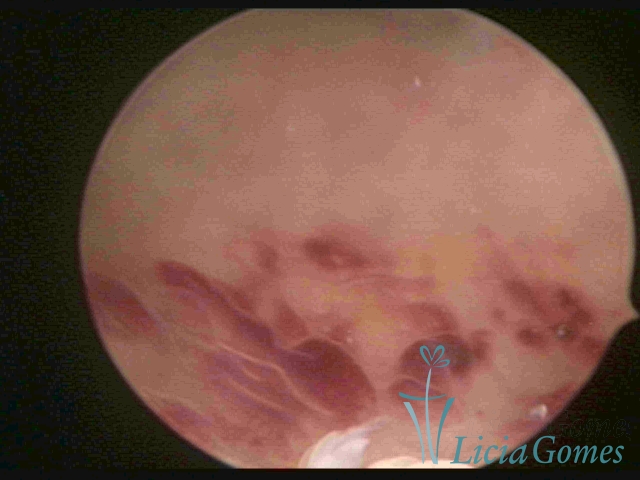

CHRONIC ENDOMETRITIS

The surface of the endometrium may present changes such as a red punctuate forming vascular balls, a smooth, hypervascularized endometrium or intensely presenting red areas, with accurate edges and yellowish white spots in its interior, providing a "STRAWBERRY PEEL" aspect, a pale yellow color of fundic and lateral commissures, in contrast with the intense red color present in the walls.